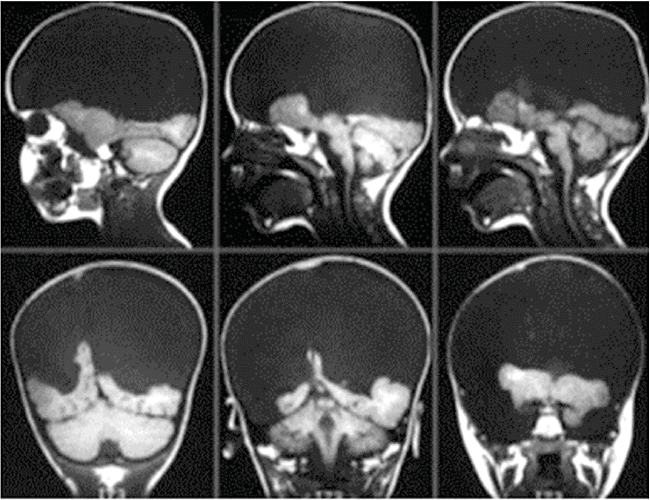

Состояние этих детей явно нельзя назвать вегетативным. Самое поразительное заключается в том, что дети с гидранэнцефалией рождаются без коры головного мозга. Обычно это происходит из-за обширного инсульта на внутриутробной стадии развития, в результате которого передний мозг рассасывается и череп плода заполняется спинномозговой жидкостью вместо мозговой ткани – отсюда название «гидранэнцефалия», что буквально означает «вода вместо мозга». Иллюстрация такого нарушения приведена на рисунке 4 (МРТ-снимок мозга трехлетней девочки, родившейся без коры). Фотографии другой девочки с таким же нарушением, представленные на рисунке 5, демонстрируют ее эмоциональную реакцию в тот момент, когда ей дали подержать маленького братика.

Рис. 4. Снимок мозга трехлетней девочки с врожденным отсутствием коры. Большая темная область внутри черепа – это место, которое должна была занимать отсутствующая ткань